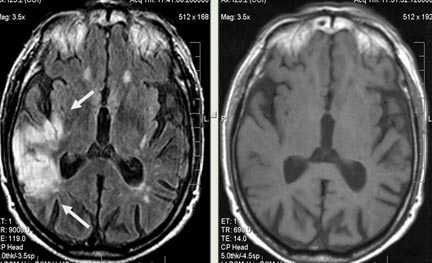

Выраженная сосудистая энцефалопатия с наличием множественных очагов хронической ишемии, лакунарных постишемических кист. Программа ДВИ четко показывает фокус острого ОНМК в базальных ядрах справа на фоне лейкодистрофии.

Характерным проявлением ДЭП на МР-томограммах является наличие множественных очагов глиоза.

В белом веществе левой лобной и обеих теменных долей, преимущественно субкортикально, выявлены множественные мелкие очаги хронической ишемии (большинство локализованных в бассейне правой средней мозговой артерии).

Проявлением хронической ишемии является также развитие выраженных дистрофических изменений белого вещества паравентрикулярной локализации - лейкоареоз.

Выраженные дистрофические изменения белого вещества паравентрикулярной локализации - лейкоареоз.